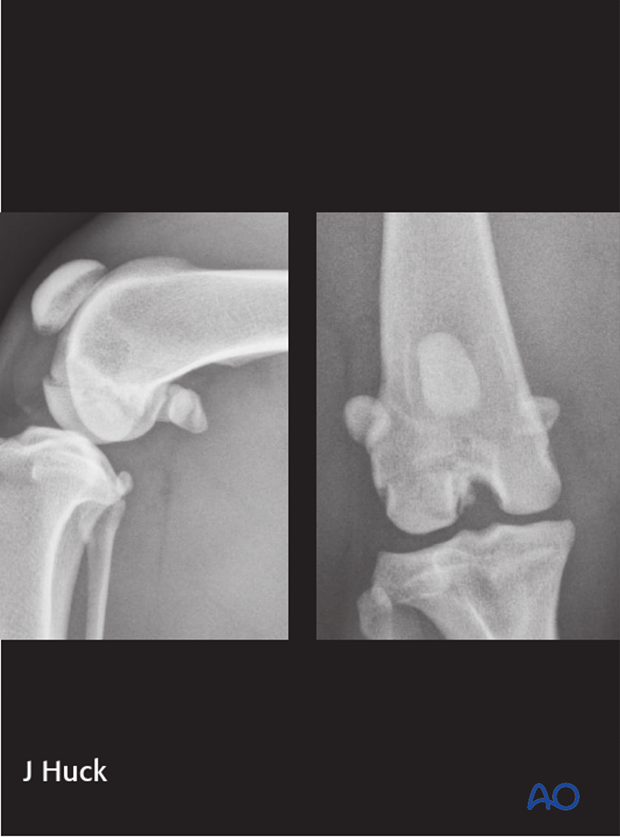

Shown are mediolateral and craniocaudal radiographs highlighting a 33-B3 fracture of the lateral femoral condyle.

Type B3 fractures are frontal plane fractures of one condyle.

Good quality mediolateral and craniocaudal radiographs are essential for fracture evaluation. If there is minimal displacement of the fragments, diagnosis may be difficult. Oblique projections and mediolateral stressed views of the distal femur might be helpful.